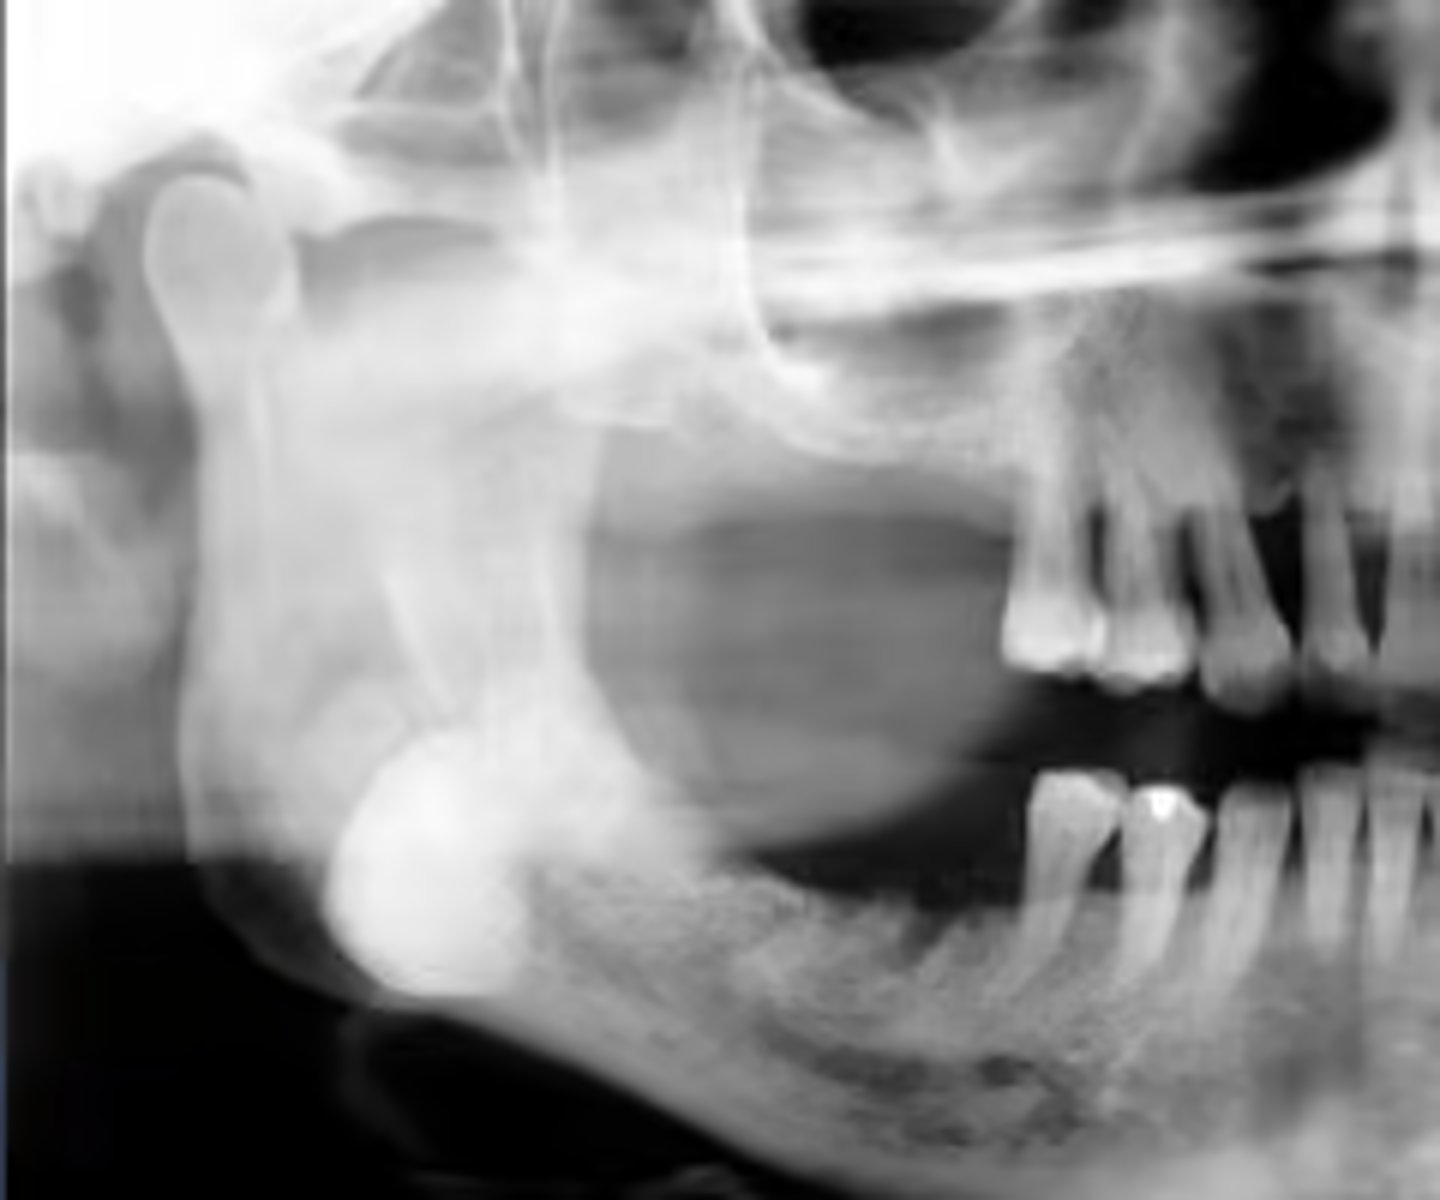

How would you describe the lesion?

- Well-defined corticated unilocular radiolucency in the left ramus causing expansion and thinning of

anterior and posterior walls of ramus, inferiorly below the inferior mandibular cortex and the coronoid process

- Dispalcement of the developing third molar.

What category would this lesion be part of?

Benign

What would be included in your D/D?

- OKC

- Unicystic ameloblastoma

- Dentigerous cyst